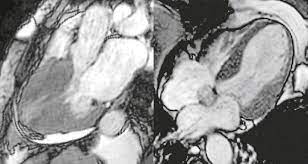

Radiologie Sachsenhausen Kardio Mrt

Radiologie Sachsenhausen Kardio Mrt from www.radiologie-sachsenhausen.de